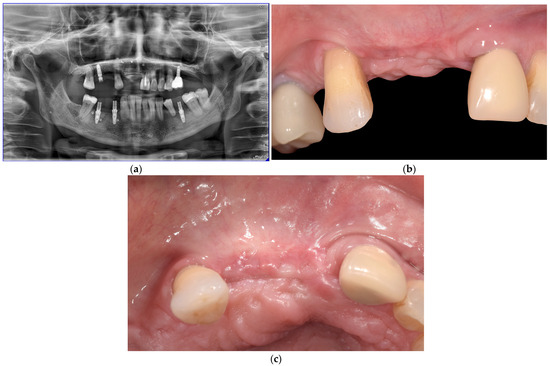

The TACOS Technique: A Stepwise Protocol for Alveolar Ridge Augmentation Using Customized Titanium Mesh

2. Materials and Methods

Surgical Protocol: The TACOS Technique

3. Results